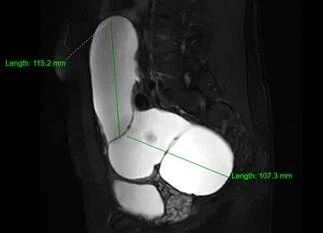

2. 影像学进一步检查:若超声无法明确,可做盆腔CT或MRI。CT/MRI能更清晰地显示假囊的位置、大小、与周围器官的关系,排除恶性病变(如卵巢癌、转移性肿瘤等)。

图片